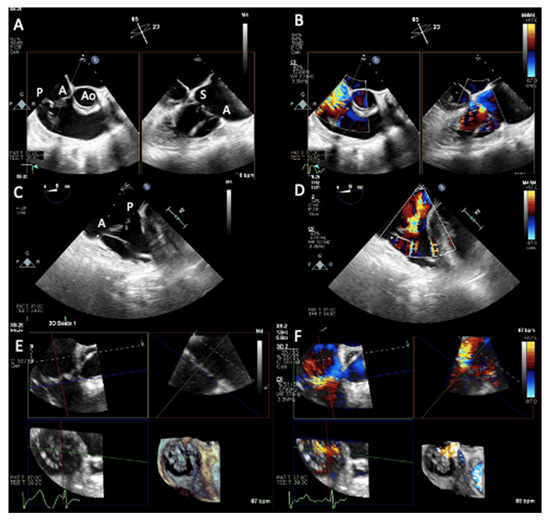

2.1. Two-Dimensional and Three-Dimensional Transthoracic and Transesophageal Echocardiography

3.1. Two-Dimensional and Three-Dimensional Transesophageal Echocardiography

4.1. Two-Dimensional and Three-Dimensional Transthoracic and Transesophageal Echocardiography